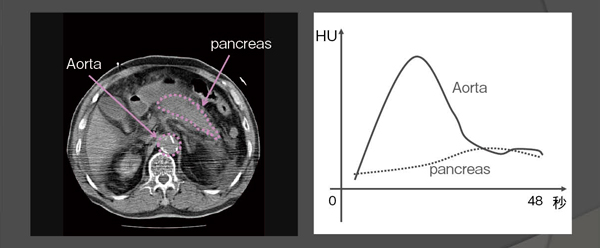

本邦では,発症早期に膵壊死診断された場合,動注療法や積極的な経腸栄養等が推奨されている。侵襲性の高い治療を適切に導入するために,発症早期に膵壊死を正確に予測する方法が必要である。そこで, われわれはPerfusion CTを導入した。Perfusion CTとは,造影剤投与後にTime Density Curve(TDC)を各ピクセルごとに解析し,Color Map化する方法である(図1)。

図1 Perfusion CTの原理